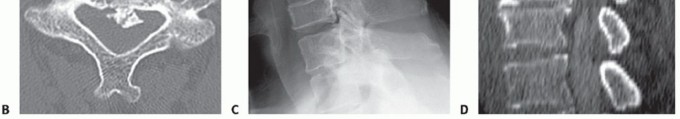

### FIG 1 • OPLL. A. Continuous OPLL causing severe spinal canal stenosis from C1 to C4. B. Axial CT scan in a different patient demonstrating a central stalk of OPLL. C,D. Congenital canal in different patients. Congenital stenosis is defined as a ratio of the canal to the vertebral body of 0.8 or less, and it can be measured on lateral radiographs (C) or advanced imaging such as CT-myelography (D). The CT-myelogram shows superimposed spondylotic changes that further narrow the canal dimensions and cause cord compression.

POSTOPERATIVE CARE If retraction time on the soft tissues of the neck has been more than 3 hours, a cuff-leak test should be considered before extubation to rule out the presence of edema that may lead to airway obstruction upon extubation. This is performed by deflating the endotracheal tube while obstructing the lumen of the tube, and then determining if there is a leak around the deflated tube. If there is no leak, consideration should be given to keep the patient intubated with the head elevated until a leak is detected. Steroids can also be given to decrease airway edema. The head of the bed should be elevated above 45 degrees in all patients postoperatively to diminish edema. Most patients are placed in a rigid cervical orthosis for 6 weeks. If a drain is placed, it should be followed closely and removed once the output is below an acceptable limit (ie, 30 mL per shift), typically on postoperative day 1. ## OUTCOMES Although the primary goal of surgery in myelopathy is to prevent progression, most patients actually note neurologic improvement after successful corpectomy and fusion.2 ## COMPLICATIONS Complications encountered during the anterior approach to the cervical spine are similar to those discussed in Chapter SP-11. The incidence of airway obstruction may be higher due to soft tissue edema from longer surgical retraction times. Neurologic injury is rare (1% to 2%). Most complications associated with cervical corpectomies are related to graft and plate problems.5 Dislodgement and pistoning of the graft into the adjacent vertebral bodies with loss of lordosis are potential postoperative complications.10 The risk increases as the number of levels corpectomized and the length of the strut graft increases. The rate of graft dislodgement ranged from 7% to 50% despite plating in one early series of multilevel corpectomy. To avoid such complications, hybrid corpectomy constructs can be used instead if the pattern of neural compression allows. Hybrid constructs combine corpectomies at levels with retrovertebral compression along with discectomies at levels demonstrating compression only at the level of the disc space (FIG 3). For a three-disc-level problem, a single-level corpectomy can be combined with a single-level anterior cervical discectomy and fusion. For a four-disc-level problem, two single-level corpectomies can be performed with an intervening intact vertebra or a single-level corpectomy with two single-level anterior cervical discectomies and fusions. Hybrid constructs avoid the negative biomechanical issues associated with long strut grafts and provide more points of segmental screw fixation, leading to constructs that are more stable and less likely to fail. If a posterior approach can be used instead in the patient with multilevel myelopathy, we prefer to do so. Ideal candidates for posterior surgery such as laminoplasty are those with multilevel cervical myelopathy, preserved lordosis, and little to no spondylotic neck pain. In patients like these, fusion and its attendant complications can be avoided altogether with laminoplasty.

### FIG 3 • Hybrid constructs. This patient had retrovertebral cord compression behind C5 and disc-based compression at C6-C7. Rather than doing a two-level corpectomy of both C5 and C6, a corpectomy-discectomy construct allows for a shorter strut graft and intermediate points of screw fixation into C6. Exacerbation of axial neck pain can occur after laminoplasty in those who have significant complaints preoperatively, although it rarely becomes of significance in those who have little to no axial pain preoperatively. Also, adequate decompression may not occur after laminoplasty in those with kyphosis, as cord driftback away from anterior compressive lesions is unreliable in this setting. ##